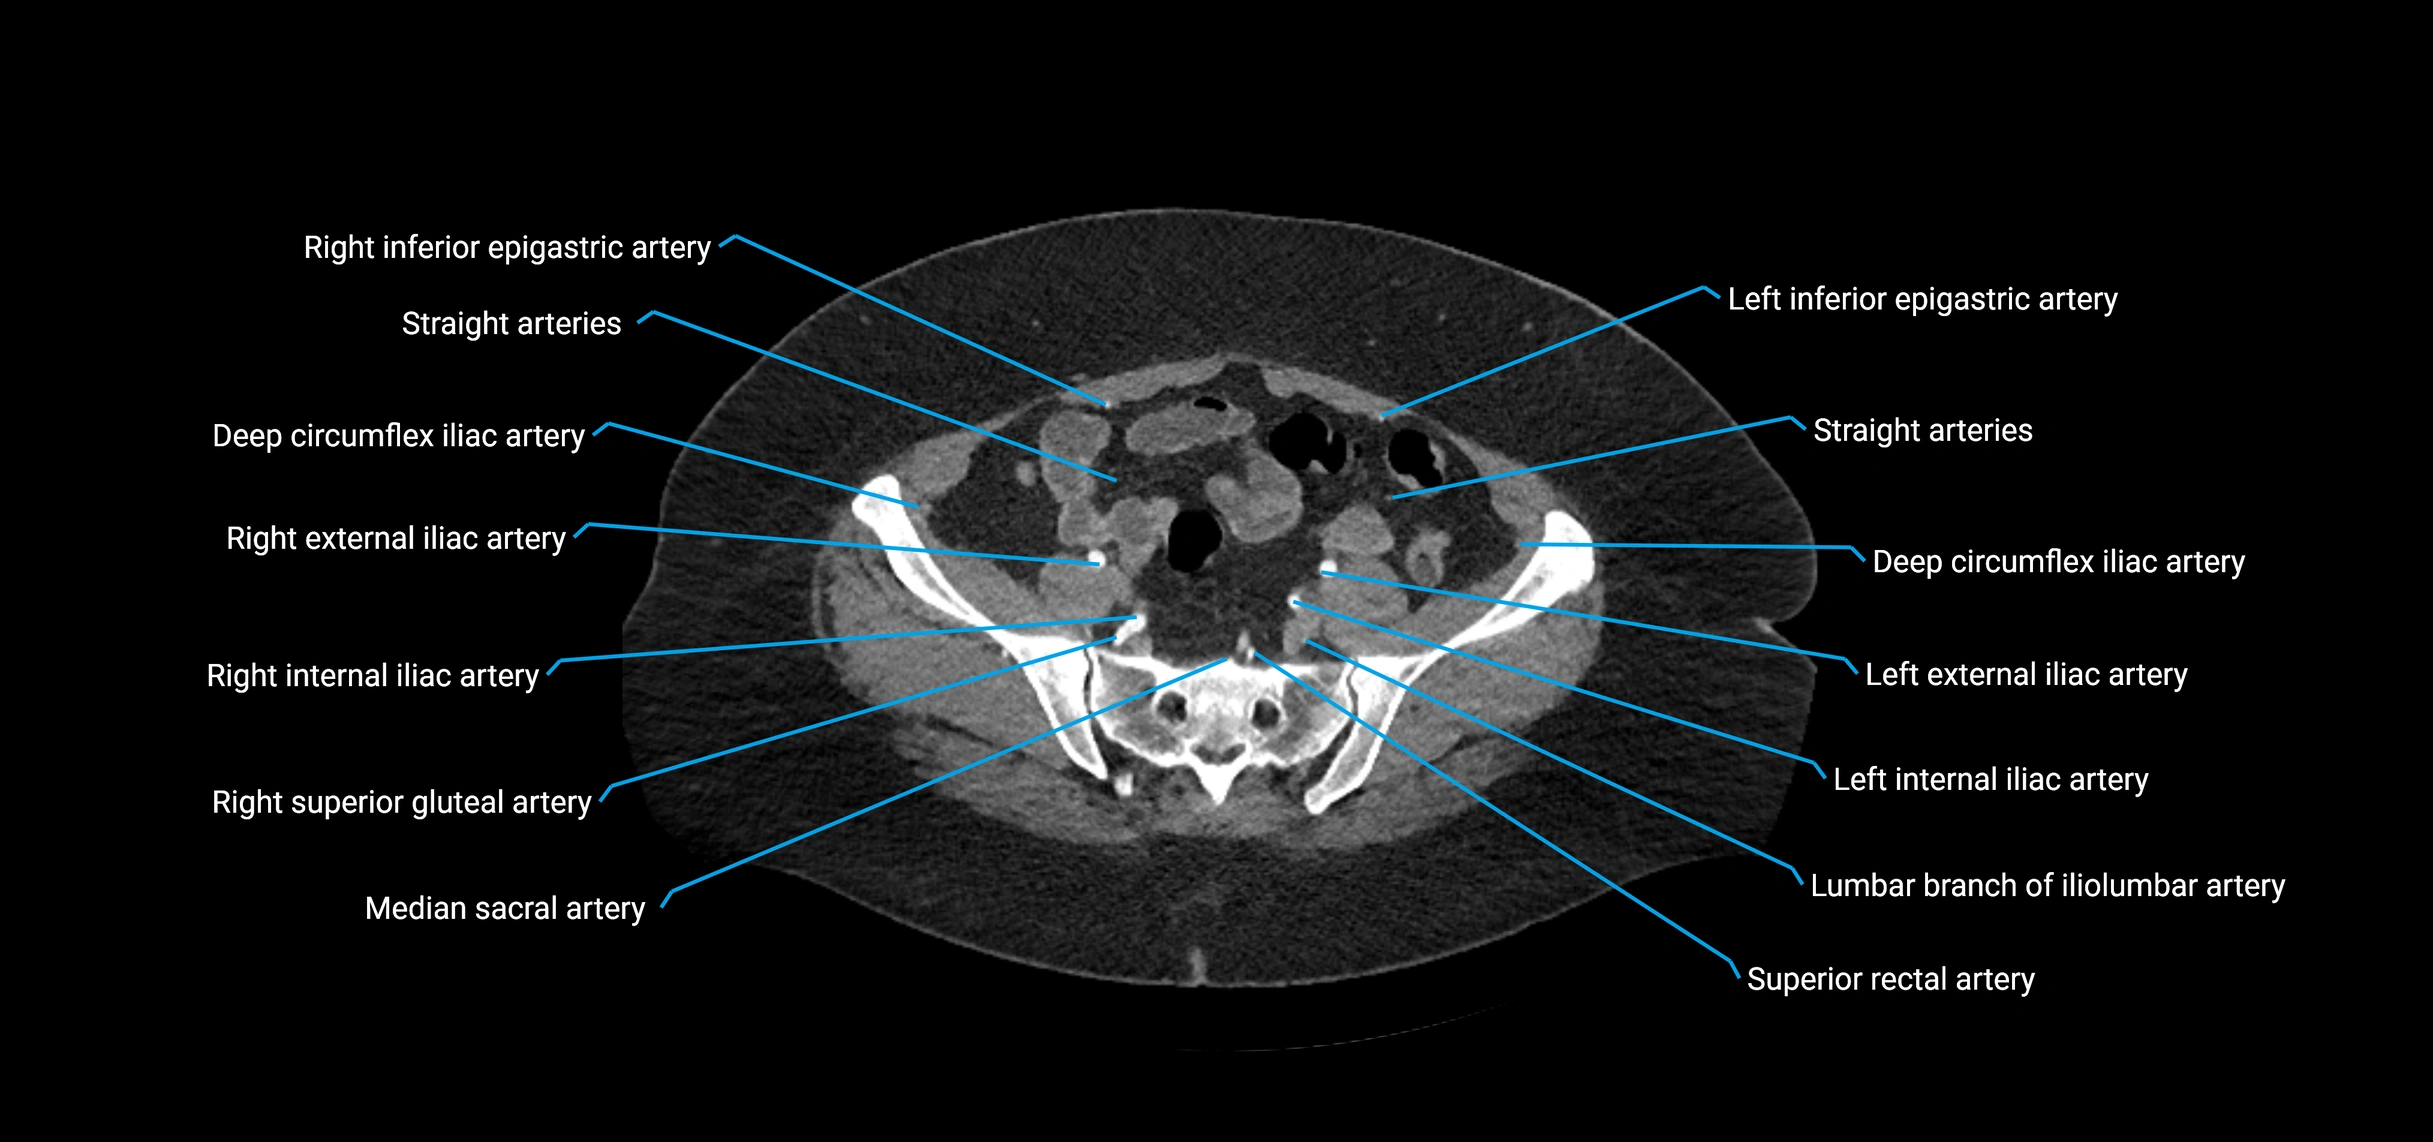

Contrast-enhanced CT (CTA):

• Gold standard for abdominal aortic imaging

• Provides excellent detail of lumen, wall, aneurysm, thrombus, and branch vessels

• Multiplanar and 3D reconstructions help in aneurysm measurement, stent graft planning, and dissection evaluation

• Detects acute rupture, traumatic injury, or occlusion with high sensitivity